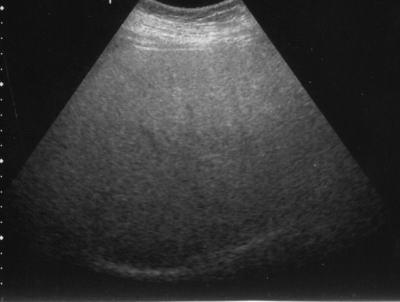

超音波の減衰

(脂肪肝でみられる深部減衰)